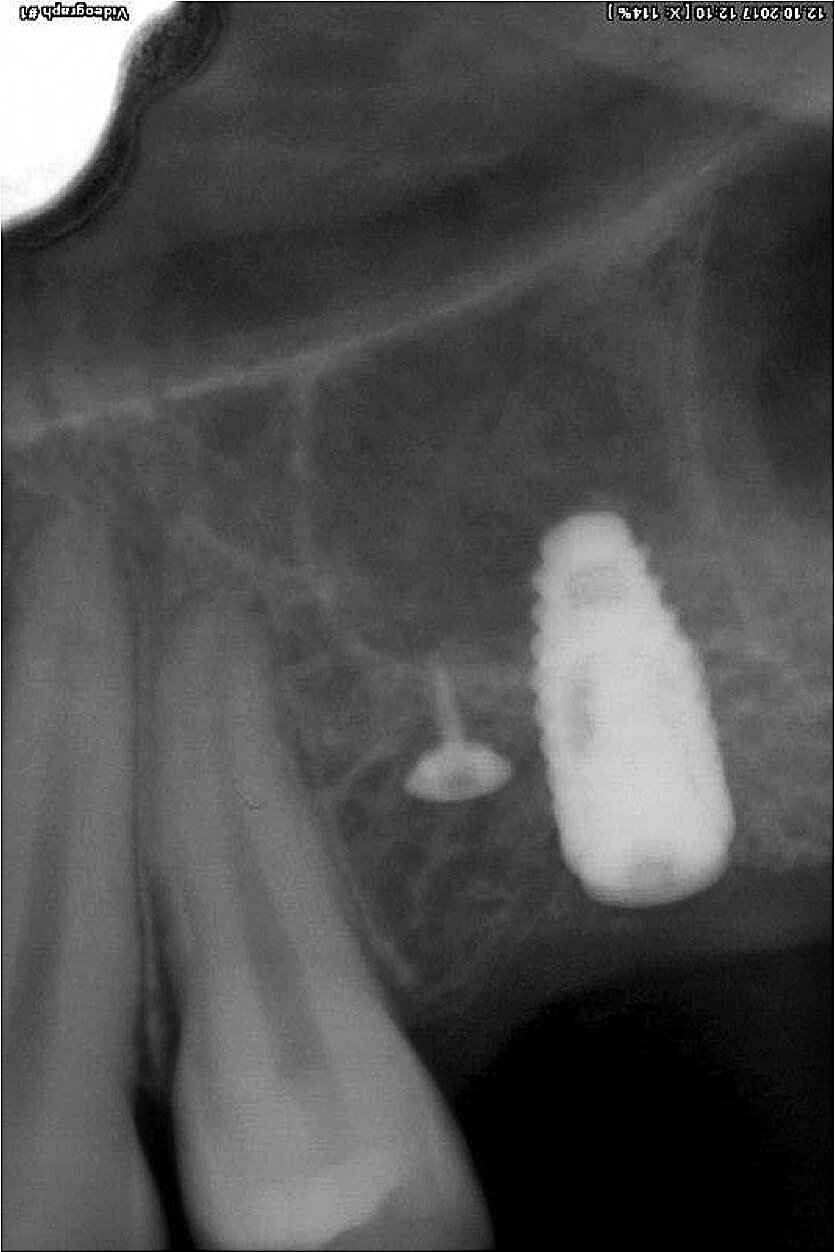

Fig. 1: Initial situation: severe bone defects and implant in situ.

The first was a 51-year-old patient who smoked 30 cigarettes per day and suffered from diabetes and stress (Figs. 1–8). The second was a 76-year-old male patient in good physical condition who smoked 40 cigarettes per day. He underwent reconstruction of the premaxilla (Figs. 9–13). The third was a healthy female patient of 24 years of age who smoked 20 cigarettes per day. She required a sinus lift in region #25 (Figs. 14–21). The patients were informed of the intended process in detail and signed the surgical protocol containing information concerning possible risks of failure and complications, as well as information on the alloplastic and synthetic materials to be used.

Digital radiographic images were taken at the time of surgery, 24 hours postoperatively and one month later in order to evaluate implant success (Figs. 6, 7, 11, 13, 15 & 20). In none of the patients inflammatory processes were found and all implants remained stable.